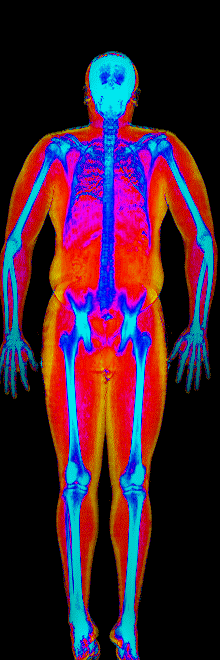

What Muscle Gain Looks Like on a DEXA Scan

Gained 21.7 lb lean · 158 → 184 lb · Age 31

Gained 12.1 lb lean, lost 9.2 lb fat · 188 → 191 lb · Age 27

Gained 9.2 lb lean, lost 6.6 lb fat · 173 → 176 lb · Age 33